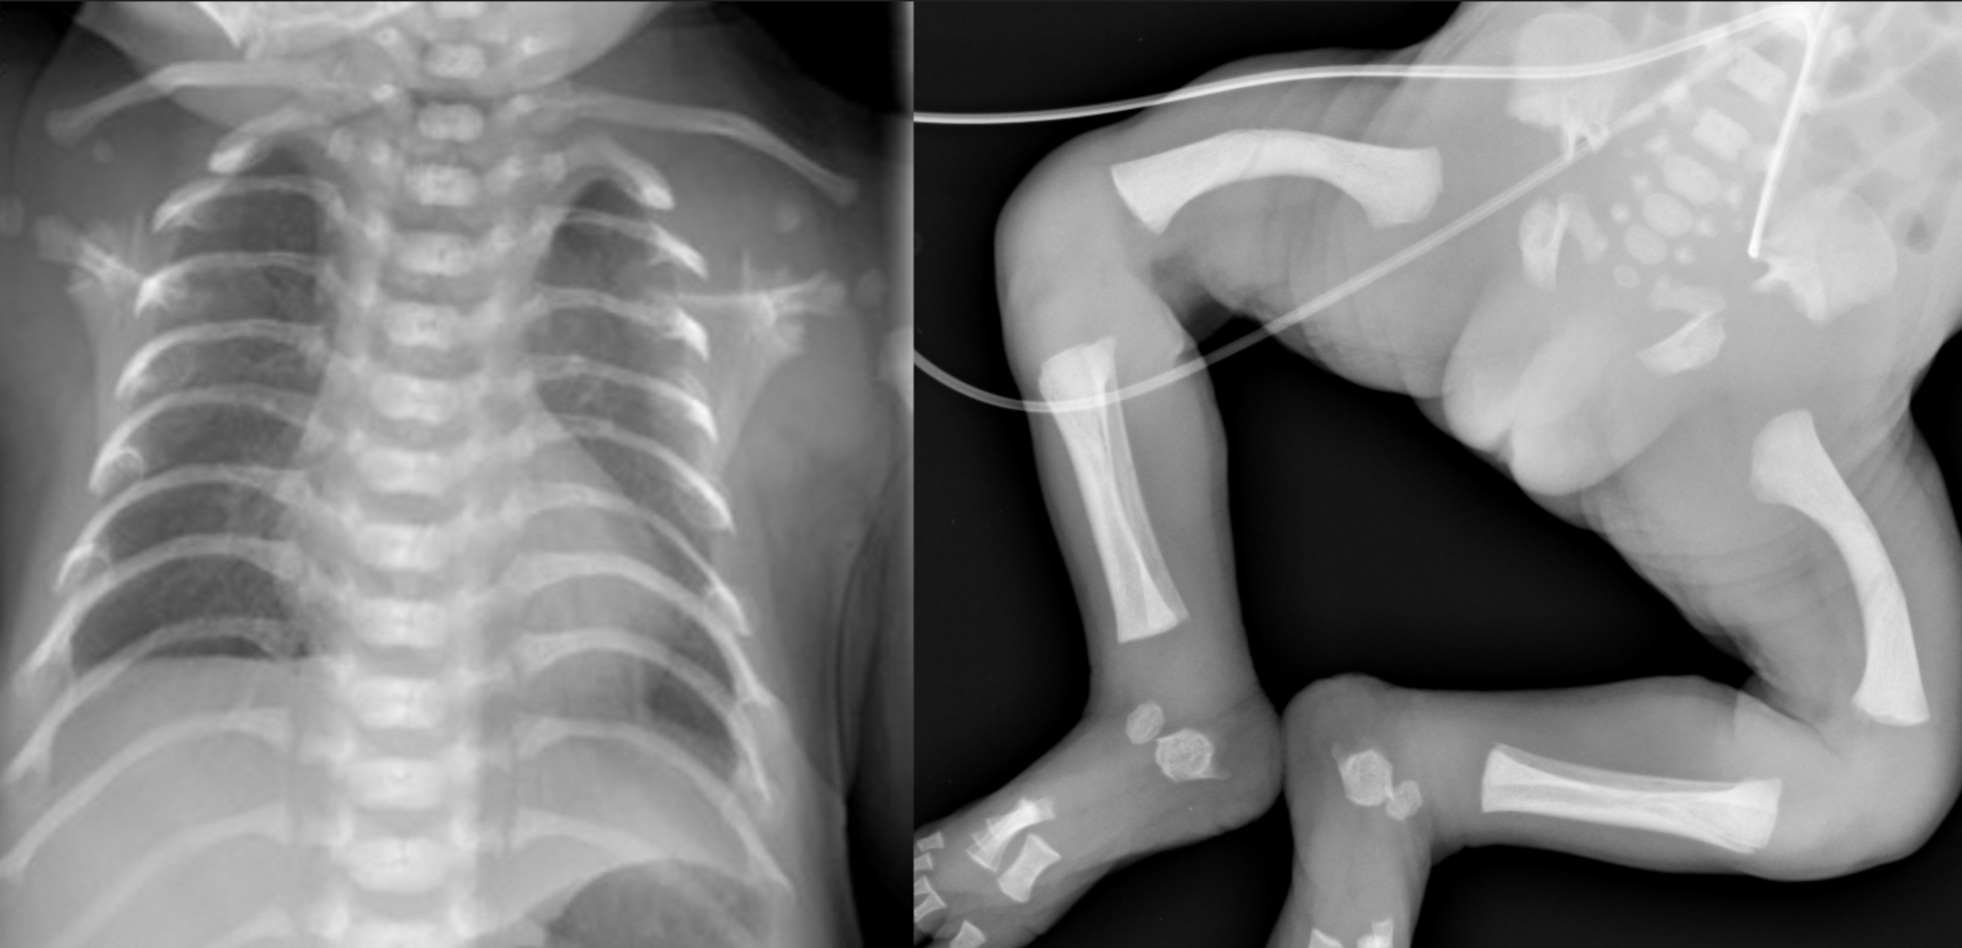

X-rays showing the narrow thorax and femoral bowing in DYNC2H1-related short rib thoracic dysplasia